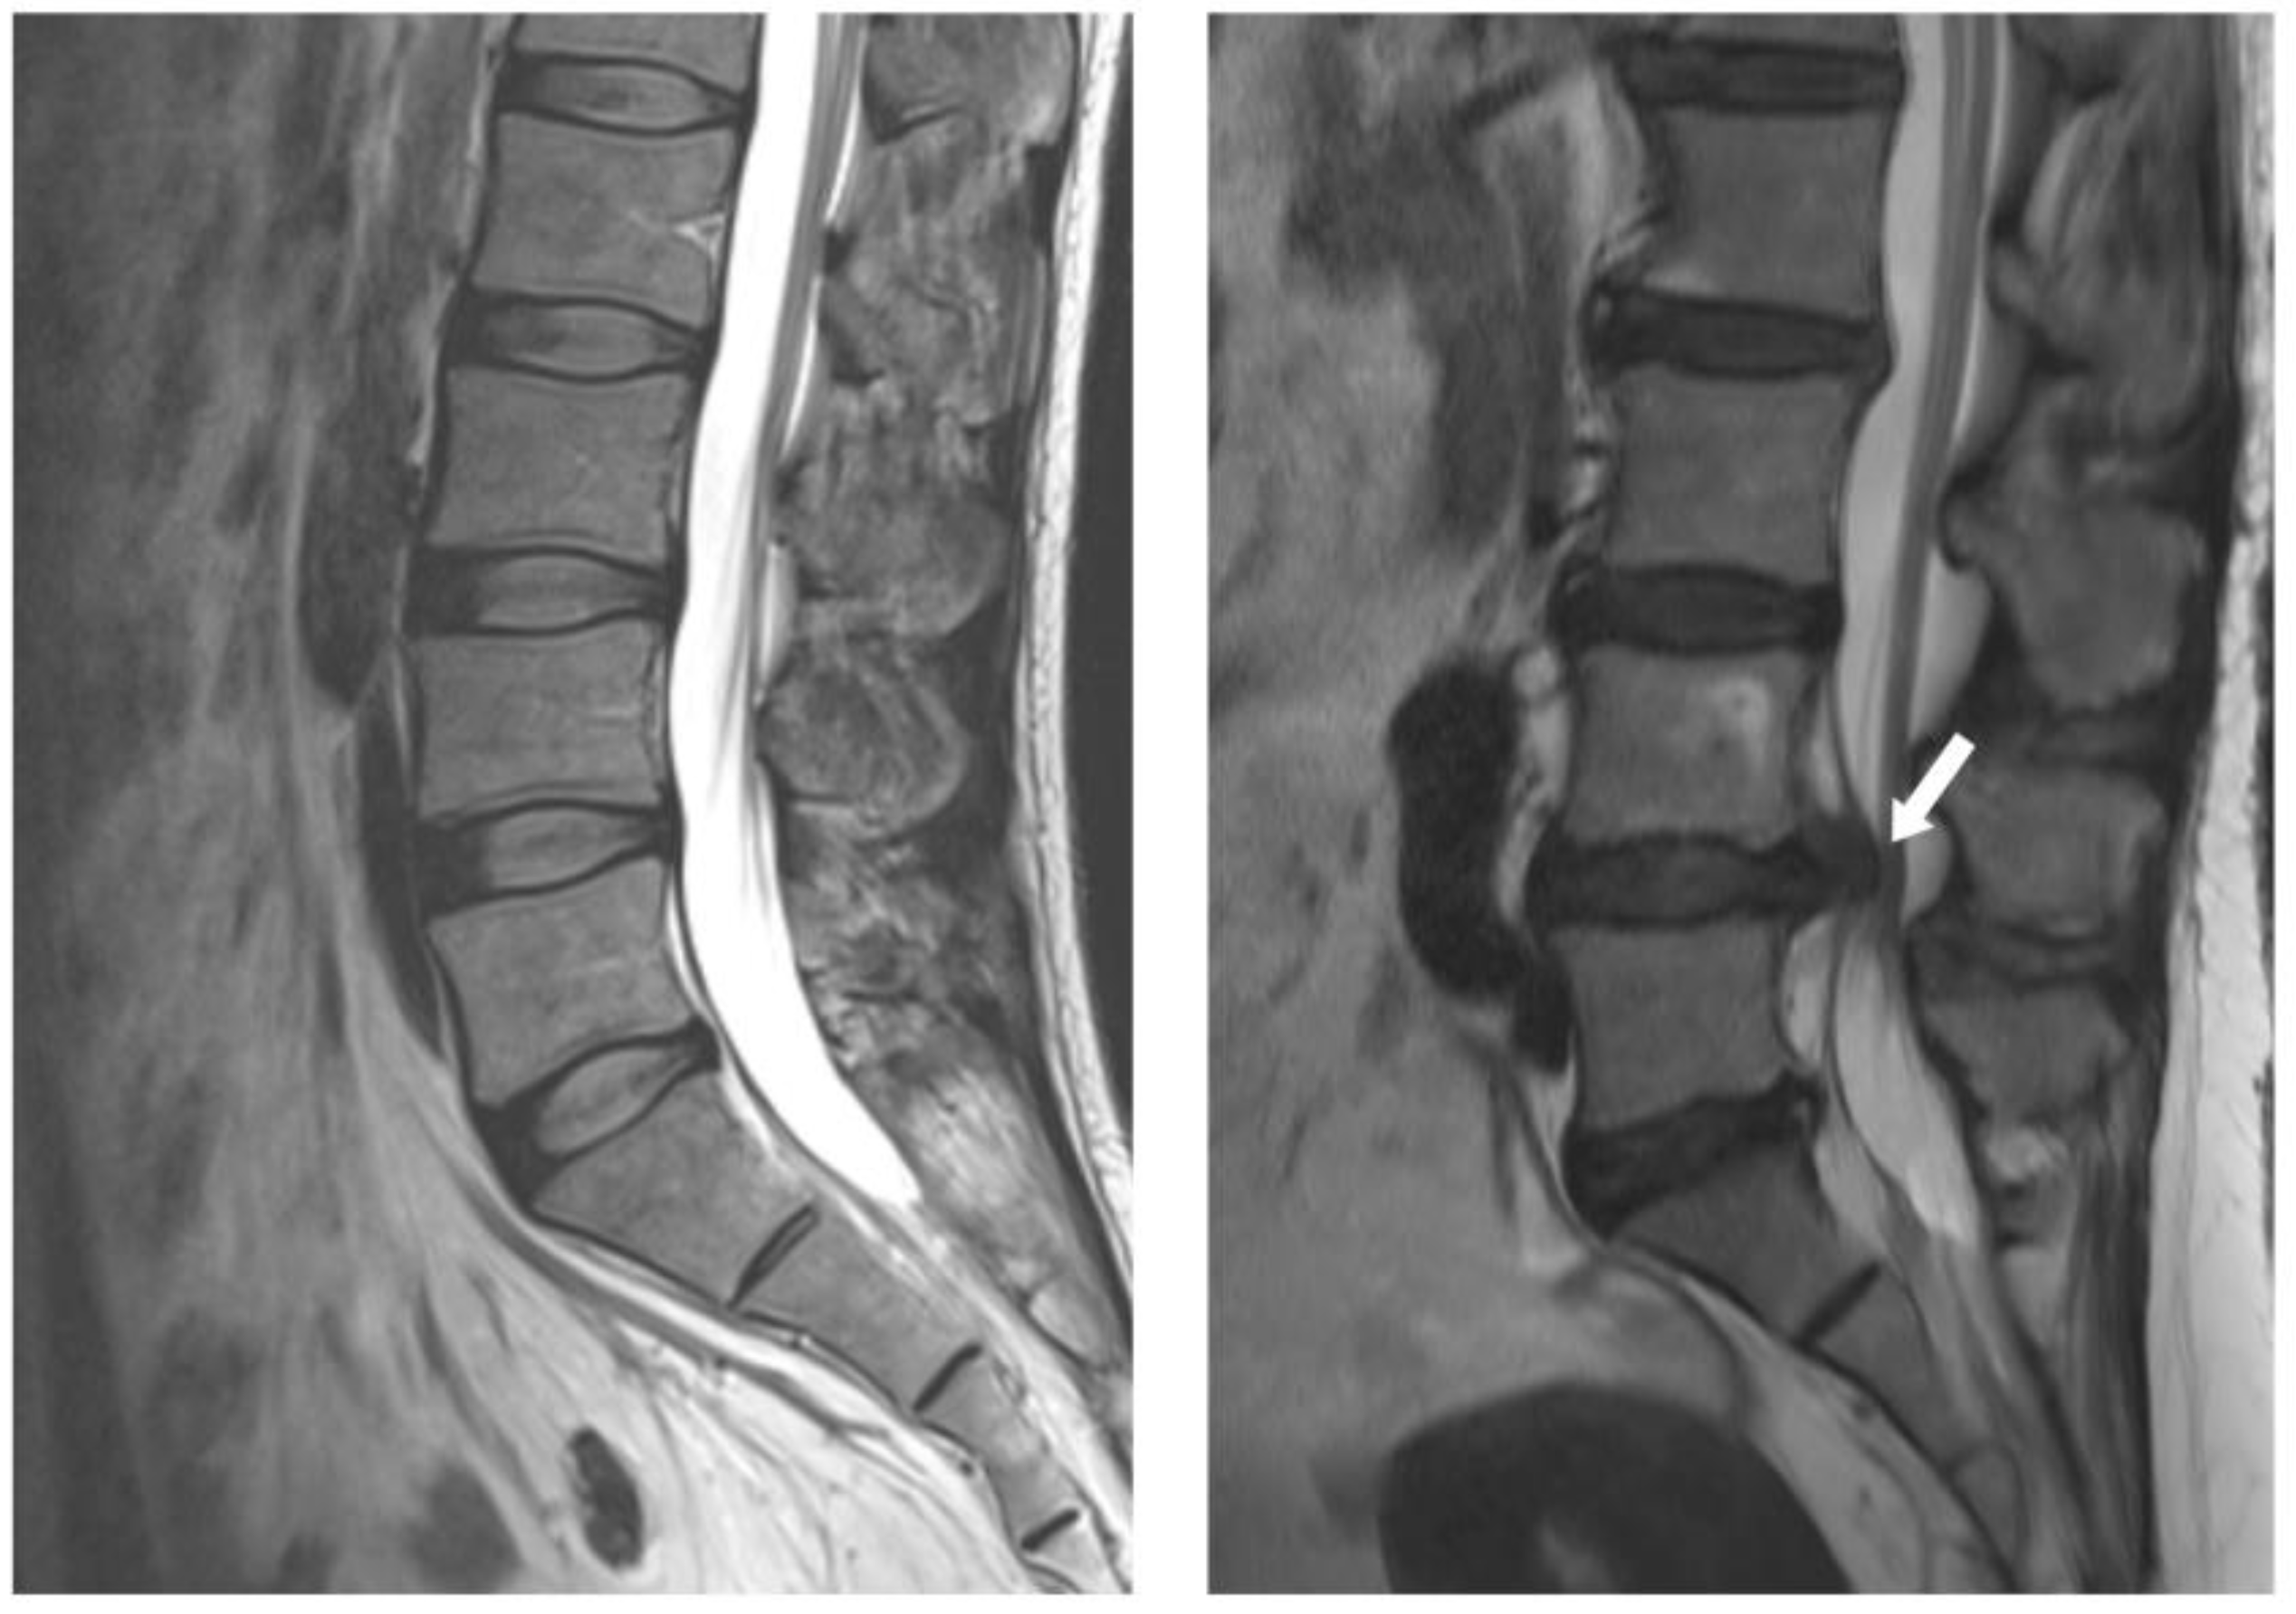

Most disc herniations occur in the lower lumbar spine, especially between the fourth and fifth lumbar vertebrae and between the fifth lumbar vertebra and the first sacral vertebra (L4-5 and L5-S1 levels) (Figure 1). In general, the first-line treatment for acute LDH is conservative therapy, which is prescribed for at least 6 weeks [15]. For nonsurgical management of LDH, NSAIDs, systemic steroids, opioids, anticonvulsants, and antidepressants are currently used to reduce pain [16]. Bed rest, an active lifestyle, and physical therapy also facilitate recovery from LDH [15]. More recently, new methods such as percutaneous ozone injection therapy have been developed with considerable improvements [17]. Most patients recover from LDH with conservative treatment without surgery [18]. However, surgery is more effective for symptom relief in cases where the patient is refractory to initial conservative treatment [19]. Predictors of failure in prolonged conservative treatment include male gender, low educational level, and intense and generalized pain [20].

Figure 1. MRI images of a normal disc (left) and a herniated disc (right).